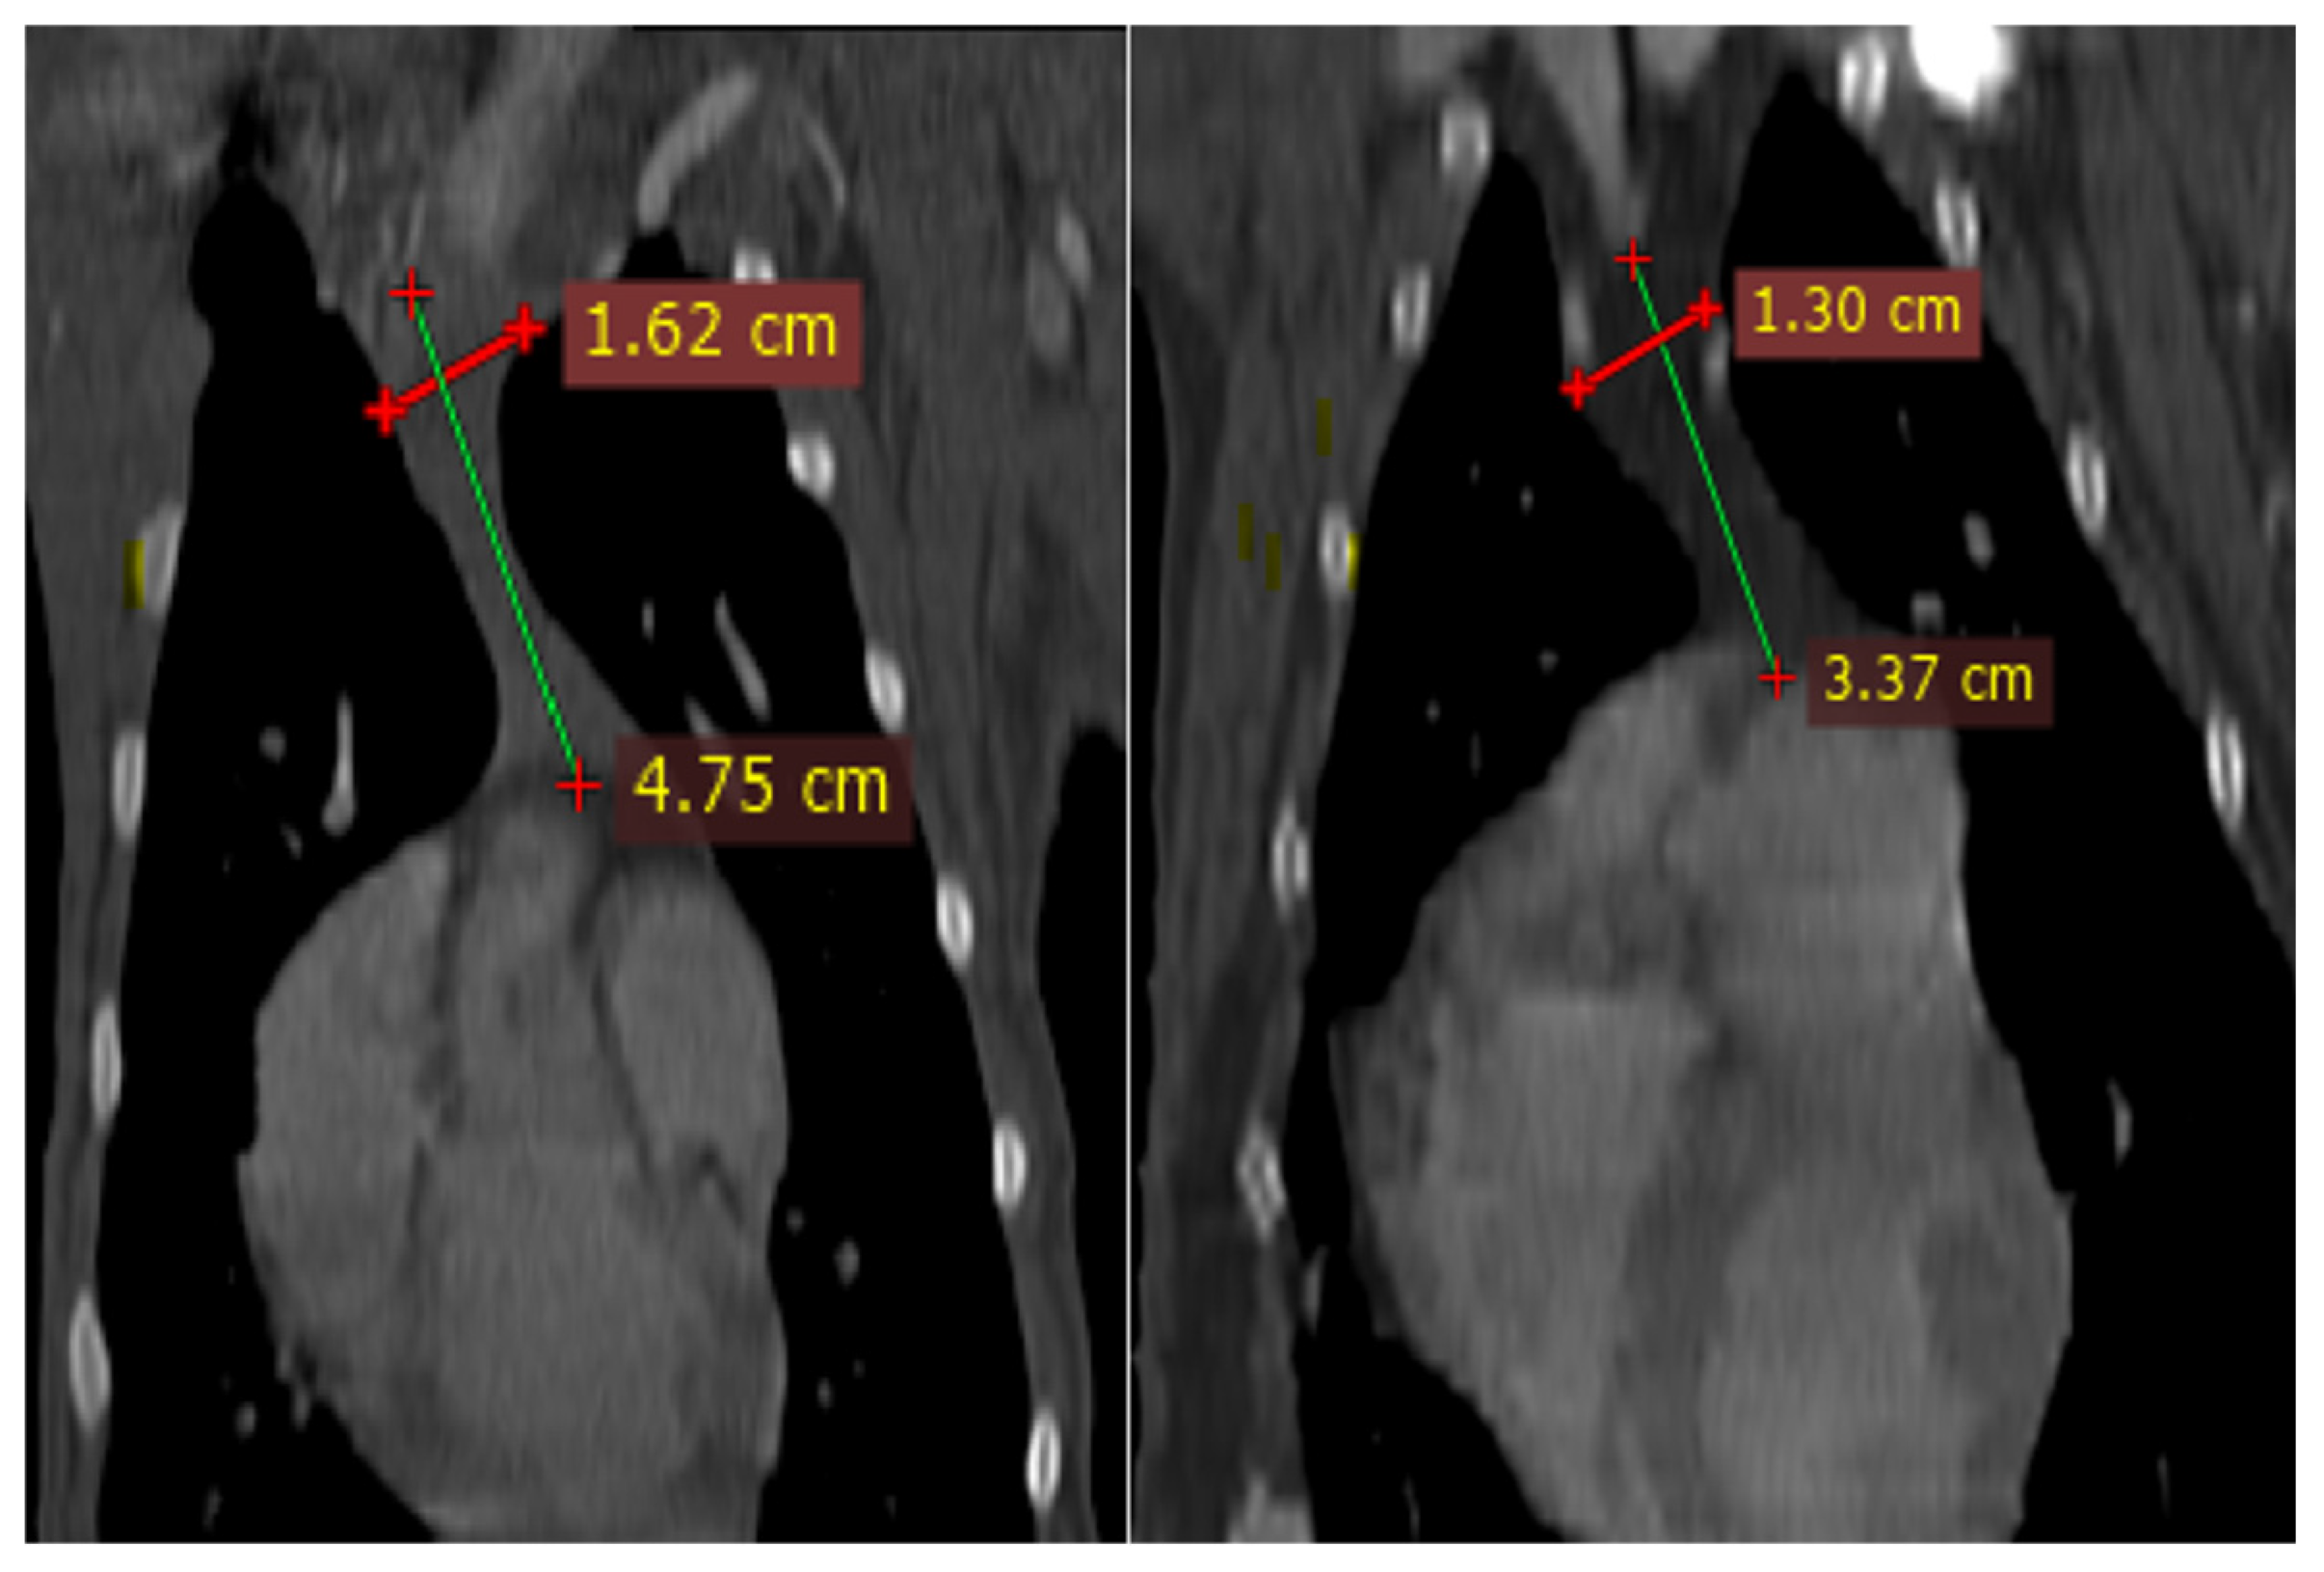

The thymus glands were evaluated in the first step to determine whether they were visible or not. Non-visible thymus glands were those with complete degeneration seen with fat attenuation and not distinguishable from mediastinal fat. After that, a grading system for thymic tissue appearance was used based on its predominant component (grade-0: totally fatty replacement of the thymus (non-visible) and could not differentiate from mediastinal fat; grade-1: more than 50% fatty replacement of the thymus; grade-2: more than 50% soft tissue component in the thymus; grade-3: totally soft tissue component in the thymus (Figure 1). After grading the thymus, the attenuation (CT number) of thymic tissue in plain and contrast-enhanced images was measured. For this purpose, a round-shape region of interest (ROI) with a surface equal to 75 mm2 was considered in the widest part of the organ for large thymus glands (Figure 2) and a smaller ROI for small thymus glands. Then pre- and post-contrast Hounsfield Units (HU) were compared for each patient individually and also between groups for evaluating the pattern of attenuation alteration.

Figure 2. Density Measurement in ROI equal to 75.48 mm2 in Plain (a) and post-Contrast (b) CT Scan Examinations of a four-month Mixed-Breed Male Dog with a Visible Grade 1 Thymus. The Thymus is Rectangular Shape with one Convex Border and is located in the midline position.